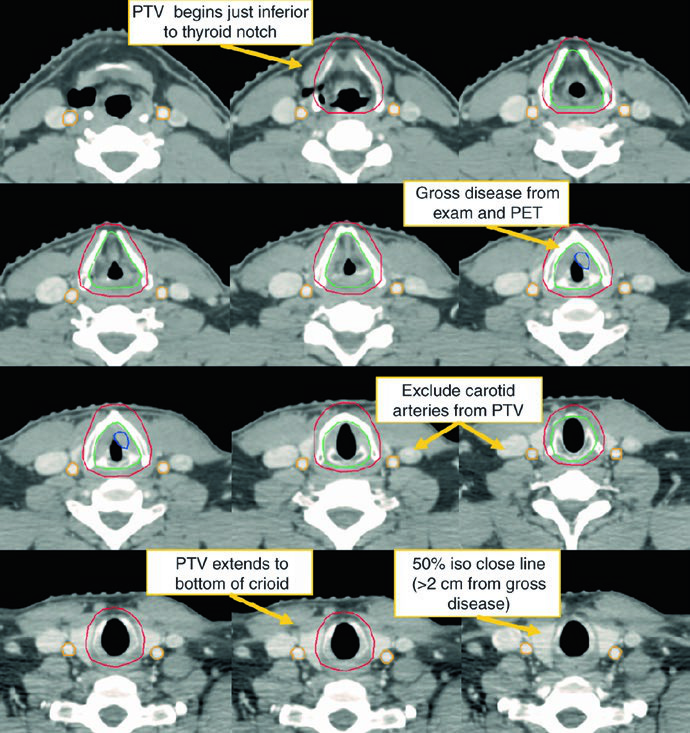

Early-stage disease: T1N0 and T2N0

For early disease, the chapter answer is direct: the CTV should encompass the entire larynx, including both commissures and the arytenoids. For T1 tumors, coverage extends from the bottom of the thyroid notch to the bottom of the cricoid cartilage. For T2 tumors, it extends inferiorly to the first tracheal ring. The inferior edge matters because many recurrences tend to track downward. In selected cases, the ipsilateral cord can be considered.

For early glottic cancer, carotid-sparing IMRT should be considered, although a CT-based opposed lateral technique remains acceptable. With laterals, the superior border reaches the bottom of the hyoid or the top of the thyroid notch, the inferior border reaches the bottom of the cricoid cartilage, the posterior border is the anterior edge of the vertebral bodies, and 1 cm of anterior flash is recommended. Beams may need a 5-10° inferior angle to clear the shoulders, and 15-30° wedges are often used to maintain dose homogeneity.

Dose is also stage-specific. T1N0 glottic tumors are treated to 63 Gy in 28 fractions because randomized data support better local control with 2.25 Gy per fraction. T2N0 glottic tumors benefit from doses above 65 Gy and fraction size of at least 2.25 Gy, so the described regimen is 65.25 Gy in 29 fractions. In selected cases, chemoradiotherapy may be reasonable.